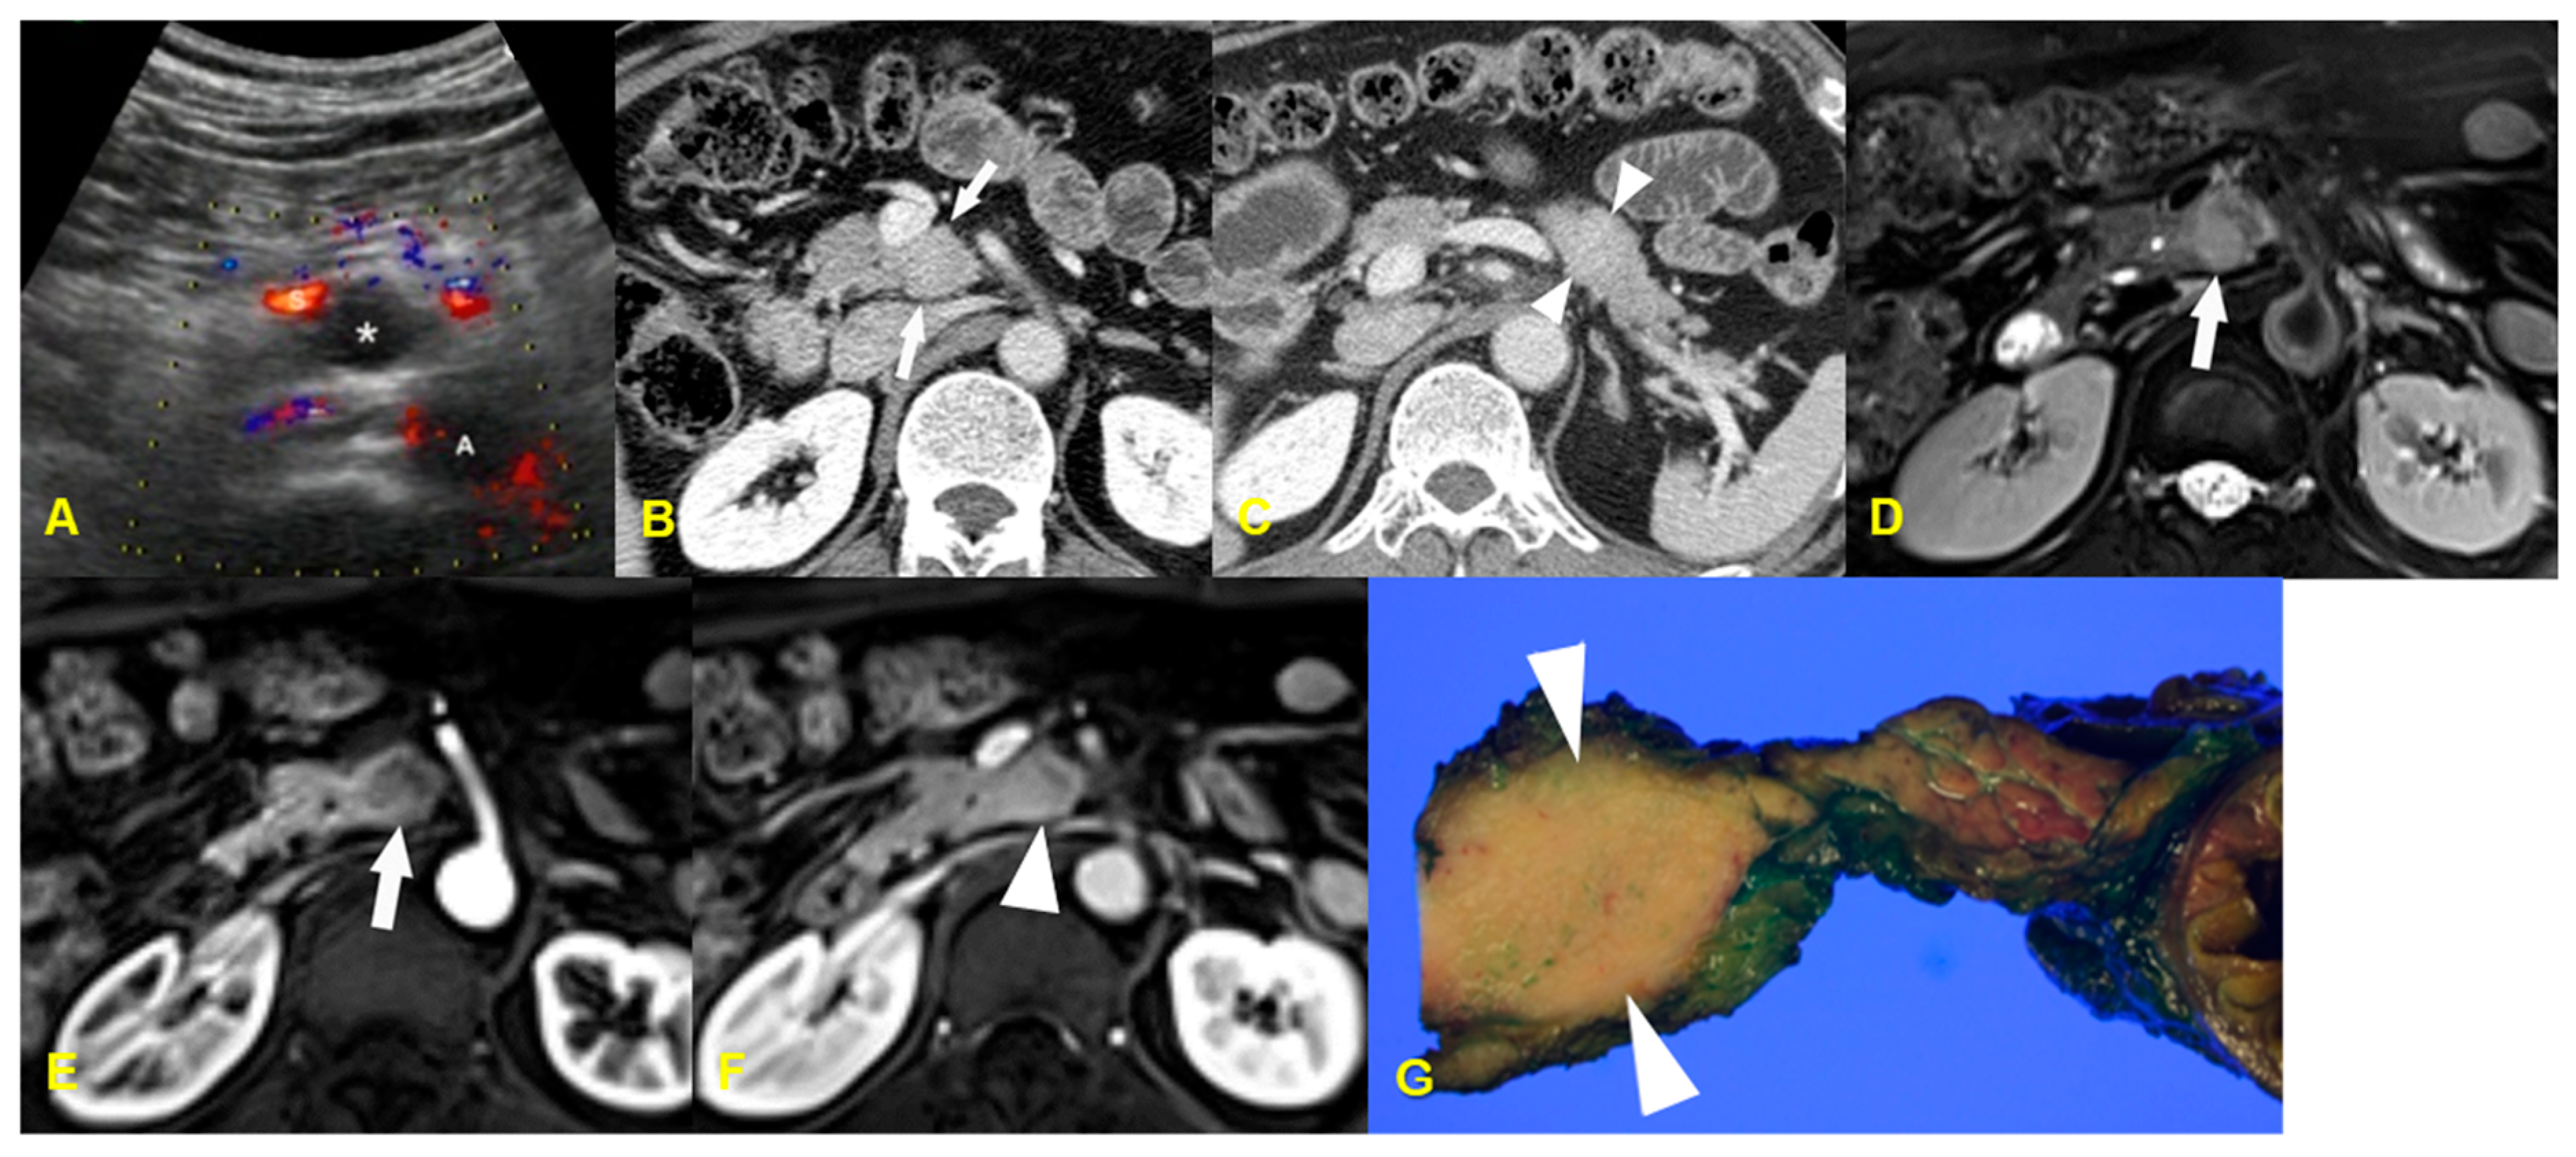

10. Infarcted Intrapancreatic Accessory Spleen

10.1. Imaging Finding

10.2. Differential Diagnosis

| Infarcted intrapancreatic spleen | Enhancement pattern: poor enhancement/ Sometimes, peripheral enhancement by capsular vessels |